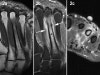

MRI : 중족골 피로골절(Metatarsal stress fracture)